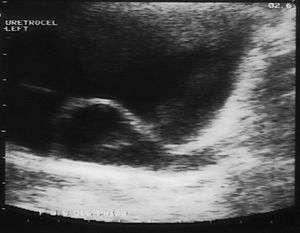

A ureterocele is a congenital abnormality found in the ureter. In this condition the distal ureter balloons at its opening into the bladder, forming a sac-like pouch. It is most often associated with a duplicated collection system, where two ureters drain their respective kidney instead of one. Simple ureterocele, where the condition involves only a single ureter, represents only twenty percent of cases. Ureterocele affects one in 4,000 individuals, at least four-fifths of whom are female. Patients are frequently Caucasian.

Since the advent of the ultrasound, most ureteroceles are diagnosed prenatally. The pediatric and adult conditions are often found incidentally, i.e. through diagnostic imaging performed for unrelated reasons.